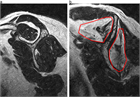

1. 肩関節の痛みの原因として、腱板断裂、石灰性腱炎、凍結肩(五十肩、肩関節周囲炎)、変形性関節症を想起すべきである(推奨度1)